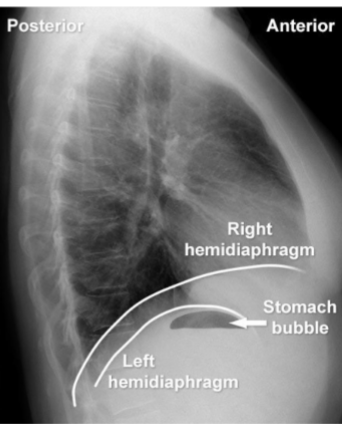

identify hemi diagrams (2) and stomach bubble

yes